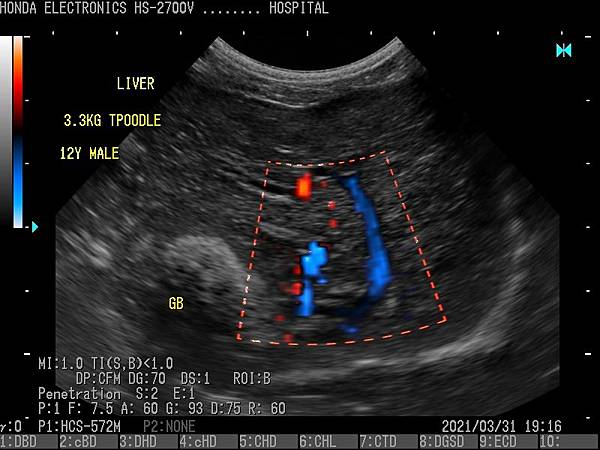

HS-2700支持CFM(彩色血流向)和PD(功率杜普勒)模式。

它們將適應廣泛的醫療應用。